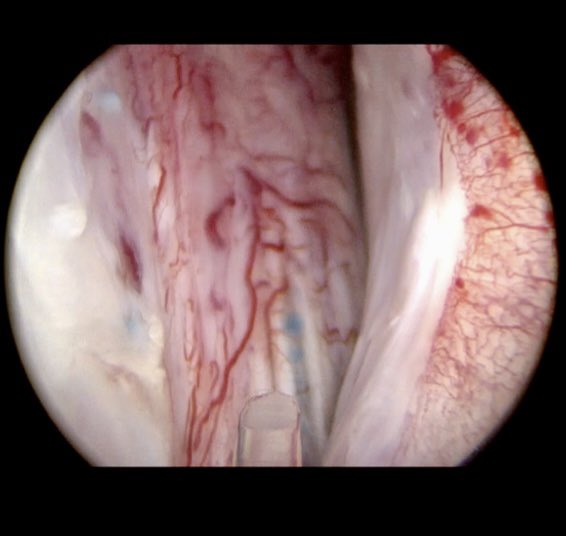

@drtevaho

Tev Aho

3 years

Tomorrow’s MoLEP case at #TNT2022 1145hr is a gentleman with severe urinary symptoms and intermittent total urinary retention which failed to improve after both #prostatearteryembolisation and #rezum. These pictures show a rezum prostatic cavity and blue PAE microspheres